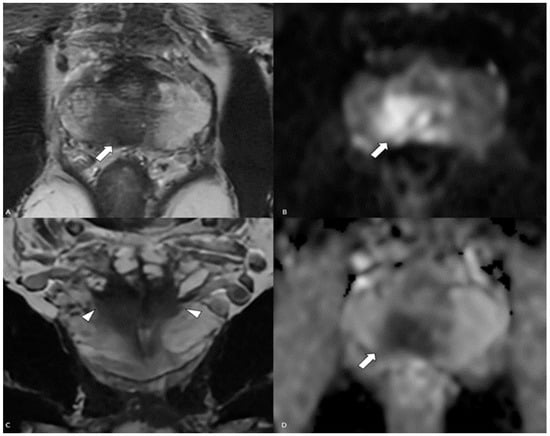

- Isharwal, S.; Devitt, M.; Gupta, S.; Mithqal, A.; Tandon, Y.K. Adenosquamous carcinoma of the prostate with low PSMA expression. Int. Urol. Nephrol. 2023, 55, 613–615. [Google Scholar] [CrossRef] [PubMed]